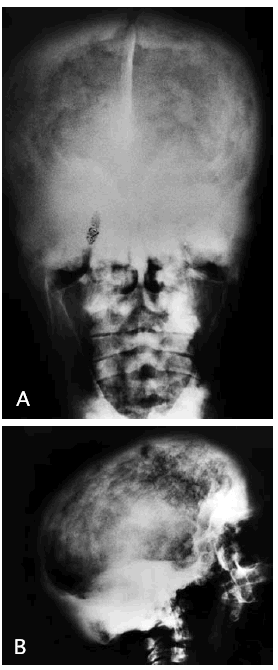

La radiografía de cráneo (fig. 1A y B) muestra importante engrosamiento de la calota craneal de manera generalizada a expensas fundamentalmente del diploe y la tabla interna. Esto condiciona una esclerosis progresiva de la base del cráneo con obliteración de los senos paranasales y pérdida de lámina dura dentaria. Con ello hay una disminución del tamaño de la cavidad craneal que puede producir compresión del parénquima encefálico, sobre todo a nivel de la fosa posterior, con cierta deformidad de las amígdalas cerebelosas a las que empuja hacia el tronco encefálico aunque no se observa hidrocefalia ni alteraciones que sugieran mielopatía compresiva. En la resonancia magnética cervical, se confirmaba la espondiloartrosis con posible mielopatía compresiva.

Fig. 1.